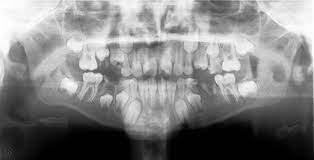

In this case report a patient with von Willebrands disease presented to the emergency room with dental trauma. A modified treatment plan taking into account the severity of the patients systemic illness and the need for medical management. This study evaluated the effectiveness of a protocol to prevent bleeding after dental extraction in patients with hemophilia von Willebrands disease VWD or platelet disorders.